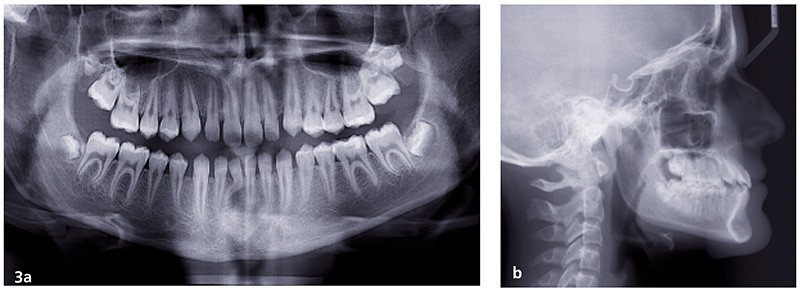

L’objectif est de rééquilibrer l’occlusion dentaire en réalisant des compensations dento-alvéolaires sans modifier le squelette. La chirurgie maxillo-faciale est écartée (fig. 3 et 4).

Il a été convenu de réaliser les déplacements orthodontiques à l’aide de la technique Insignia pour optimiser la gestion du torque et la coordination des arcades.

La gestion du set up se fait avec une contrainte principale : l’adaptation dento-alvéolaire à la latéromorphose mandibulaire. Cela va nécessiter des angulations de torque asymétrique entre les secteurs droits et gauches des arcades. L’utilisation de brackets Damon métal à torque individualisé de la technique Insignia est parfaite pour gérer cette contrainte.

La deuxième difficulté est la correction de l’articulé inversé qui sera gérée par une bonne coordination des arcs possible par la fabrication d’arcs individualisés dès le 14×25 CuNiti.